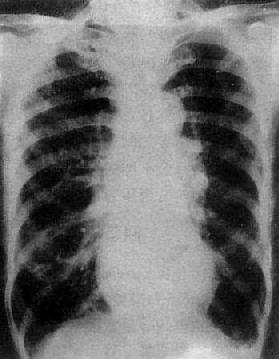

图3-2-15 二尖瓣狭窄

A.右前斜位:右心室增大,肺动脉段突出(↑),心前间隙变窄(↑),左心房轻度增大;B.后前位:心增大,呈二尖瓣型,右心室增大,肺动脉段突出,左心耳增大,出现第三弓(↓),有肺瘀血表现;C.左前斜位:右心室增大,左心房增大不明显;左心室不增大。